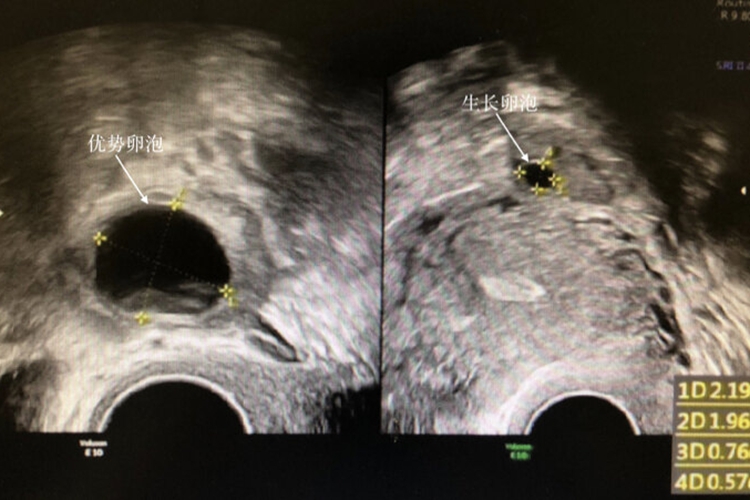

3、拮抗剂方案:通常在月经周期的第2-3天开始促排,当卵泡直径达到12-14毫米时,添加拮抗剂来防止提前排卵。